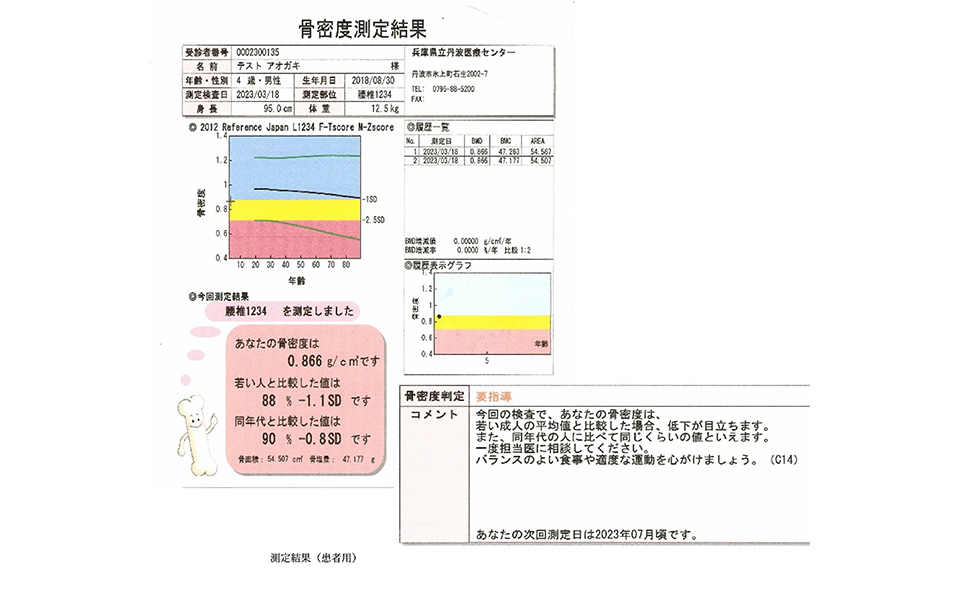

⾻塩定量検査部⾨

骨塩定量検査とは、骨組織の骨量が加齢と供に減少し、腰や背中の痛み・骨折などを起こしやすくなる骨粗しょう症の診断を主に行う検査です。X線を照射し直接骨量を測定するDEXA(デキサ)法で腰椎・大腿骨などを撮影して骨量を測定します。今年度(令和5年)、新たに東洋メディックの「Horizon」という装置を導入しました。これにより、今までよりも高精度な骨塩定量検査が可能となっています。